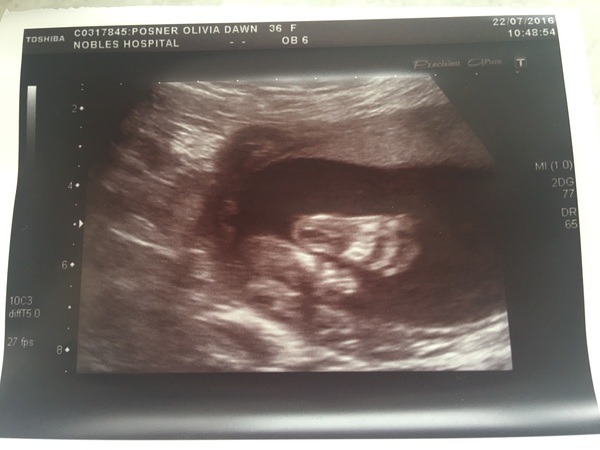

This is my favourite pic from my scan Smile

December 2016 babies - thread #4 - blooming in trimester 2!

IslandLife · 25/07/2016 15:49

I'm 20 weeks today, so I think I need to be more patient. Bump is really low and I feel like a kangaroo carrying around a baby in a pouch! Confused